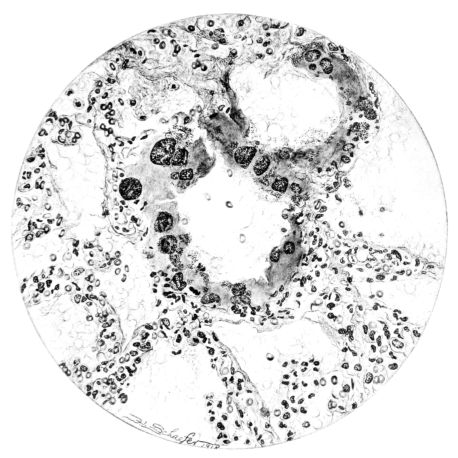

FIG. XXVI. AUTOPSY NO. 103. THE LARGER ILLUSTRATION OF AN HEMORRHAGIC ALVEOLAR EXUDATE IS ELABORATED BY TWO HIGHER POWER DRAWINGS. THESE SHOW (1) AN ANEURSYMAL DILATATION OF A CAPILLARY IN THE ALVEOLAR WALL AND (2a) A RUPTURE OF THE CAPILLARY WALL WITH THE ESCAPE OF RED BLOOD CELLS INTO THE ALVEOLUS; (2b) NECROSIS WITH EARLY THROMBOSIS OF THE CAPILLARY IN THE ALVEOLAR WALL.

As might be expected from the gross appearance, the alveoli vary in size. At times slightly collapsed and at other times overdistended, their lumina are still the seat of the inflammatory exudate, although the mechanical change may allow of some variation in the appearance of their walls. As a rule, however, the alveolar wall is prominent and owes its conspicuousness to the tortuous, engorged vessels within. These vessels contain red blood cells almost exclusively, and on account of the partial, occasionally complete, loss of the lining epithelium, the alveolar wall appears as a huge, dilated arteriole (101) separating the lakes of coagulated material in the spaces (Fig. XXIII). There are areas, as indicated above, where the alveolar content may be more definitely arranged in the form of beaded or homogeneous strands of different caliber; the smallest resemble delicate threads. They tend to converge toward the alveolar wall like wheat in a sheaf, and often pass through this wall by way of the so-called pores of Cohn; as soon as the body of the neighboring alveolus is reached, they again present a fan-like expansion into innumerable, fine strands (Fig. XXII). Where the exudate is more fibrinous, the alveolar wall is less likely to be distended, its vessels are not so prominent, and their content of red blood cells is definitely decreased. Still this is not the most extreme type of alveolar exudate met with at this stage. Perhaps, the most striking, although not the most frequent, exudate has a superficial resemblance to a huge, red blood clot, and it may be difficult to make out the alveolar walls separating the masses of well preserved red blood cells that fill the alveolar spaces. These areas are indistinguishable from infarcts and may be associated with thrombotic arteritis in near-by pulmonary vessels (47) (Figs. XXIV and XXV). Among the red blood cells an occasional strand of fibrin, a desquamated alveolar epithelial cell, and rarely a polymorphonuclear leucocyte may be encountered. The alveolar wall itself varies in the definition of its outline. When its vessels are greatly distended, when its alveolar epithelium is gone, and when its content consists largely of red blood cells, it is difficult to distinguish from the exudate which it encloses. However, when it is more compressed or when its epithelial lining cells are still more or less intact, it may be seen as a blue-staining strand under the low power of the microscope, for the well preserved nuclei lend it prominence.